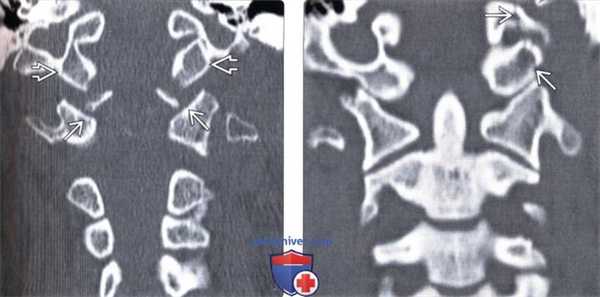

4. КТ перелома мыщелка затылочной кости:

• Костная КТ:

о Прямая визуализация переломов мыщелков затылочной кости о ± сочетанные переломы основания черепа, атланта и/или осевого позвонка

о ± атланто-затылочный подвывих

(Слева) КТ, аксиальный срез: отрывной перелом нижнего края правого мыщелка затылочной кости, фрагмент смещен медиально.

(Справа) На фронтальном КТ-срезе у этого же пациента также определяется небольшой отрывной перелом нижнего края правого мыщелка затылочной кости. Также здесь виден косой перелом правой боковой массы С3.